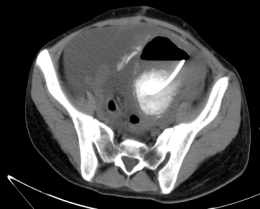

术后危机:患者术后出现高热、腹腔引流管引流出浑浊液体,CT证实十二指肠水平部瘘。因营养不良合并重症感染患者病情恶化。

2024年肝胆胰脾外科成立外科重症治疗组,派4名高年资医护人员赴东部战区总医院(原南京军区总医院)重症医学科进修学习。危急时刻,正在南京进修的卢俊杰副主任医师立即启动绿色通道,24小时内完成患者航空转运。南京专家团队采用肠瘘修补、黎式双套管冲洗引流、跨瘘口营养支持。经过42天治疗,患者每日瘘口引流量从500ml降至20ml,达到转院标准。